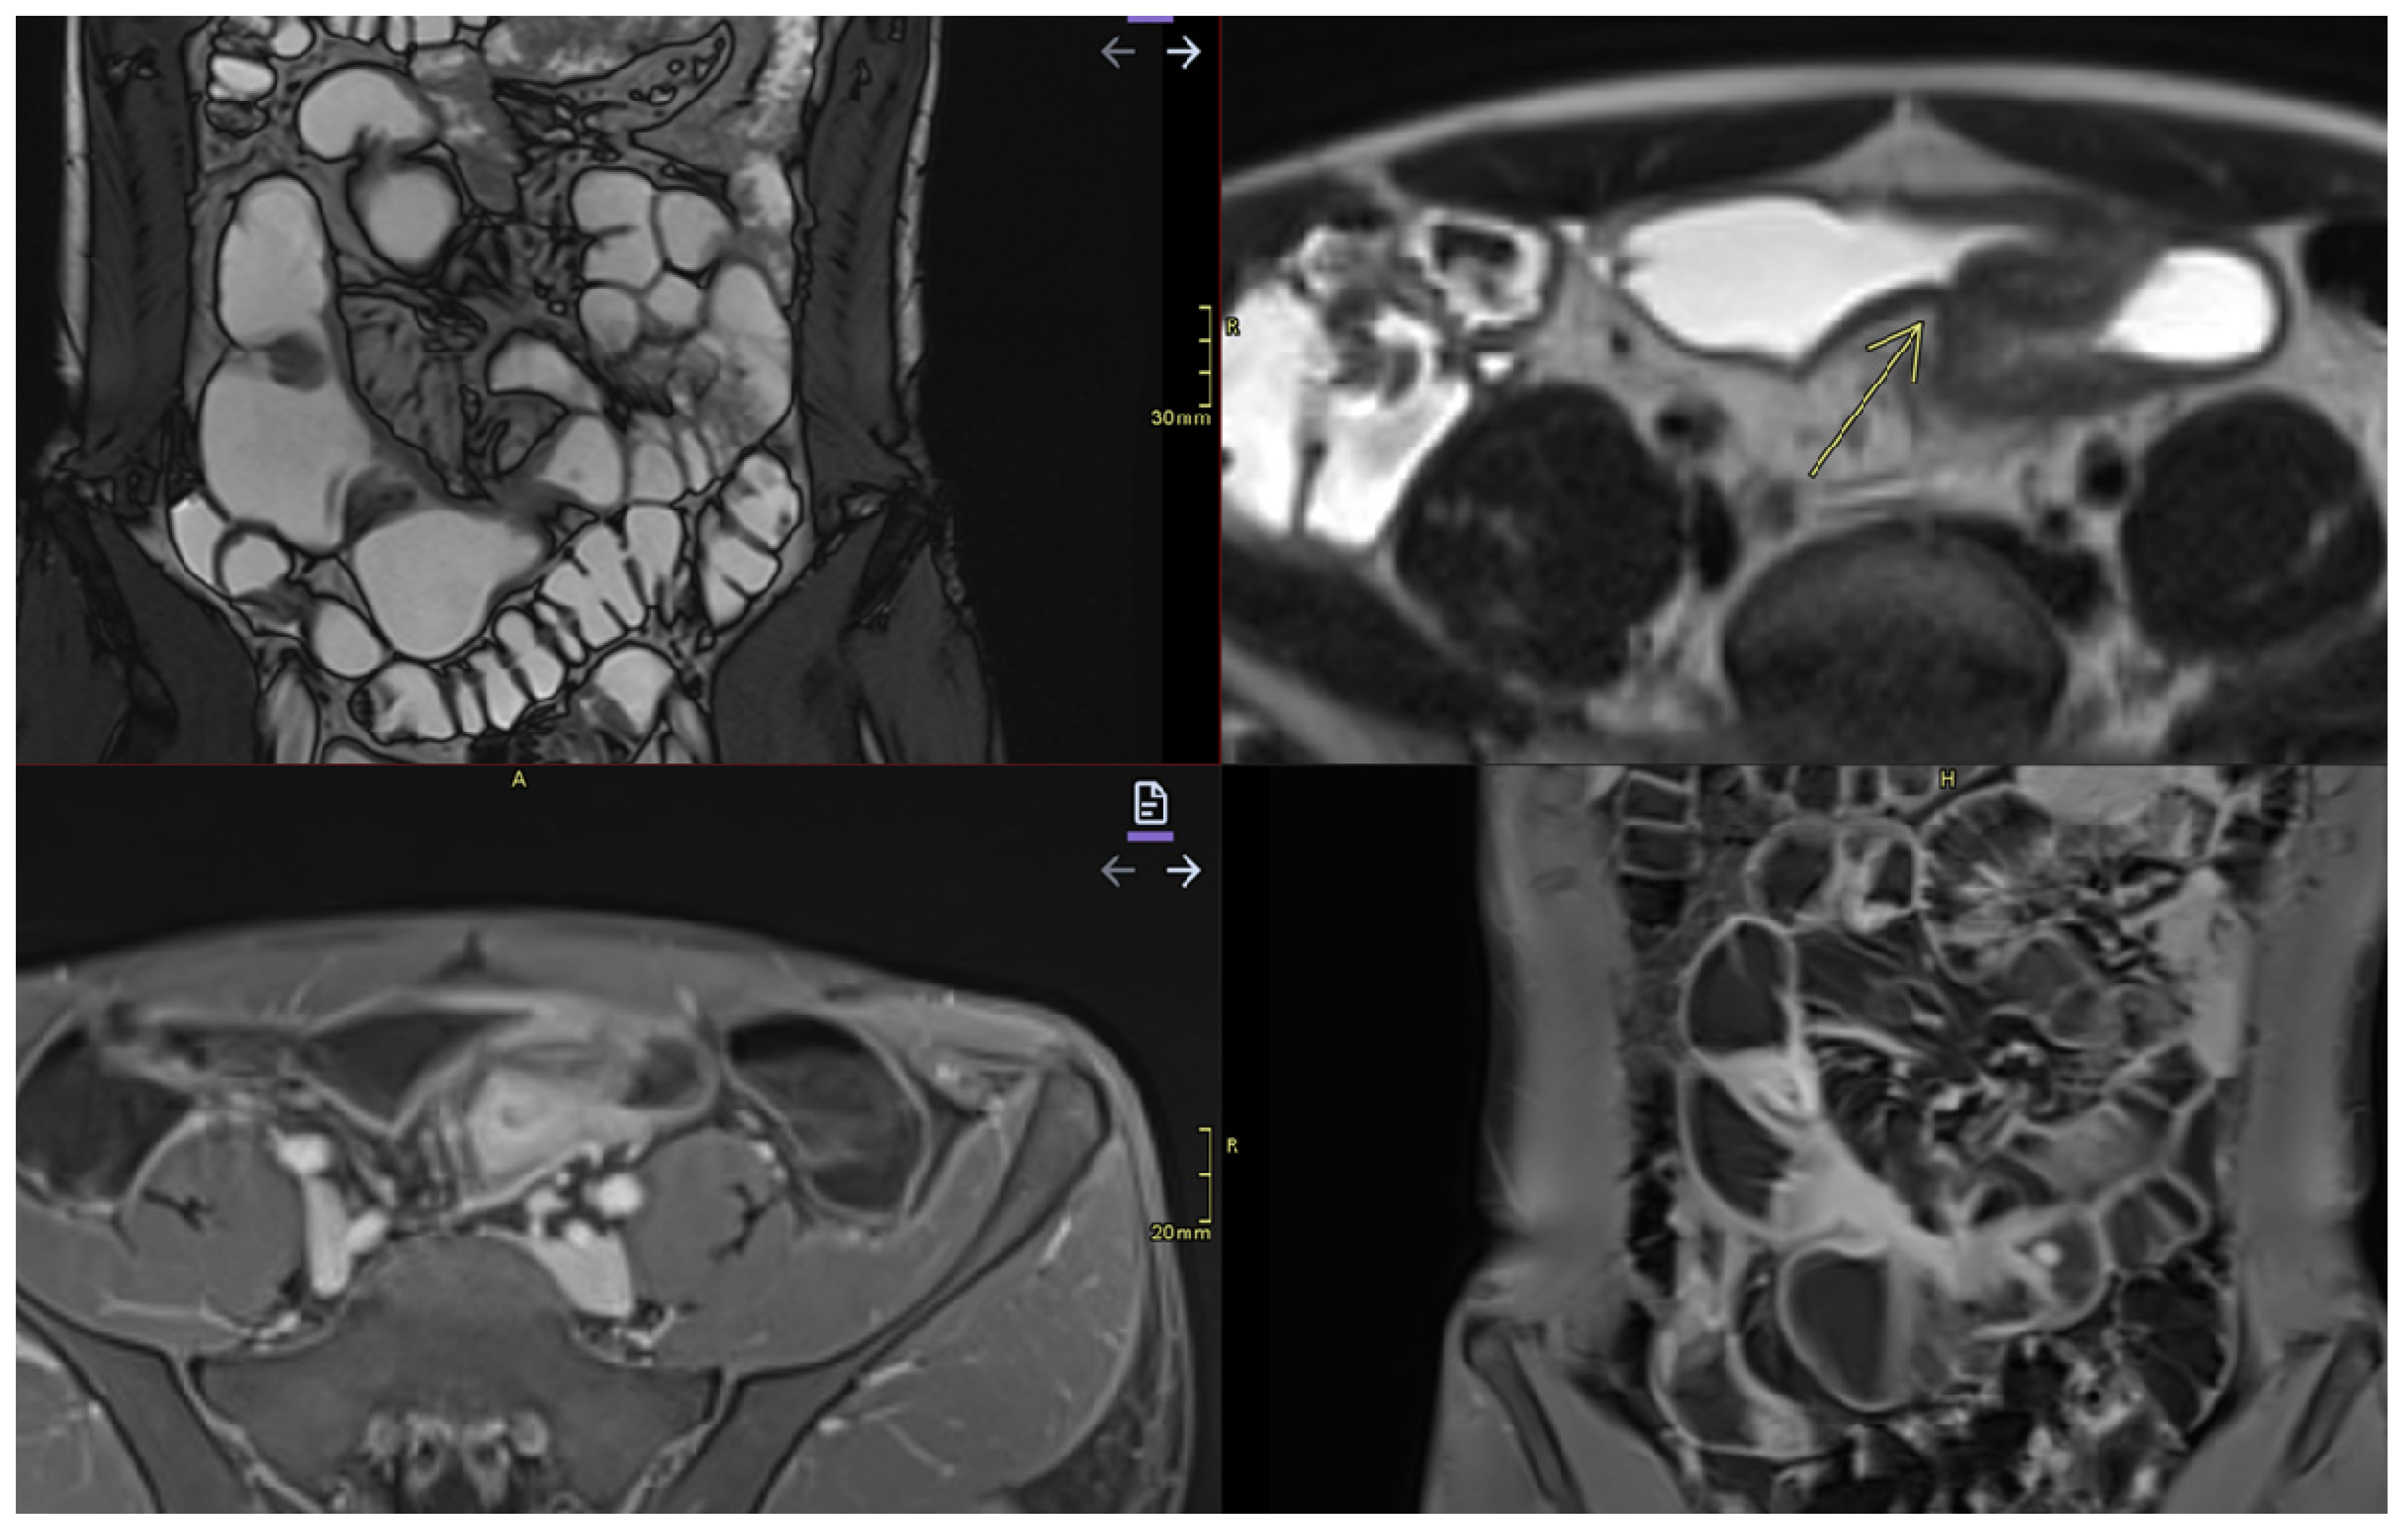

- Mural thickening:

- Can be mild (<5 mm), moderate (<9 mm),orsevere (>10 mm).

- Commonly occurs in active areas of inflammation (Figure 1).